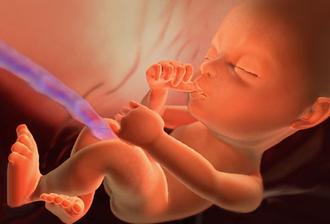

23.5. pro průkazku + odběr krve + utz 11+0 mimisek 4,2cm